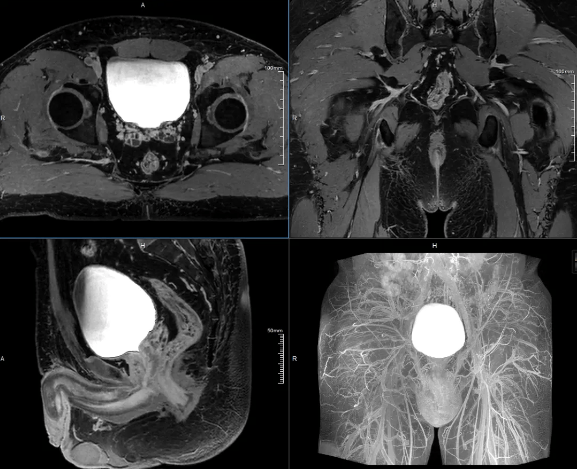

12月,高尚健康集团上海中心与上海长征医院携手,以“基于PET/MR一体化影像数据及AI后处理的盆腔解剖学三维重建手术规划的临床实践与应用”为研究方向,通过对上百例患者开展结直肠专项筛查,完成了相应的科研论证工作。